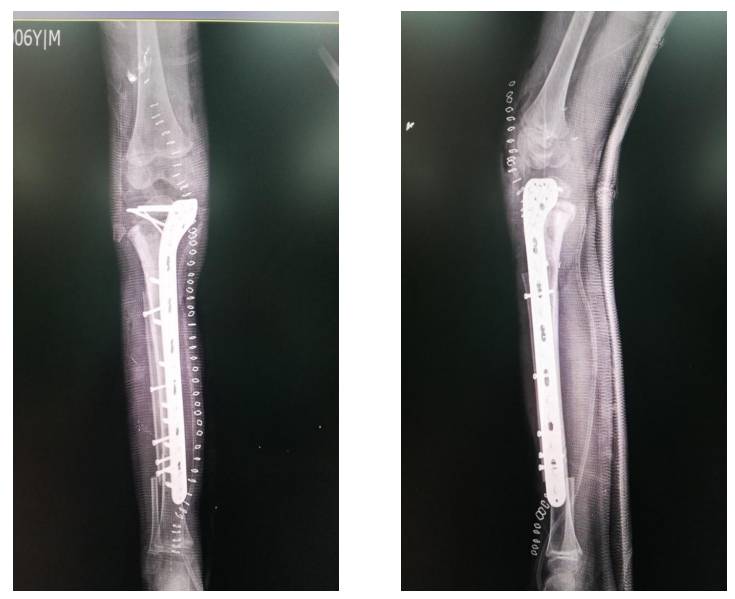

Ameliyat Sonrası: Röntgende rezeksiyon sonrası geri kazanılmış kemik ve fibulanın titanyum anatomik plak ile fiksasyonu görülmekte